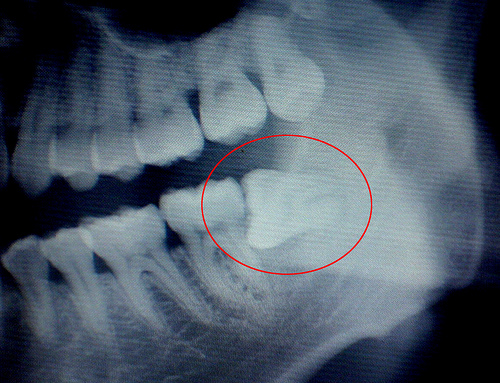

生活中,人们可以通过以上这些症状来判断自己是否长有智齿!但由于智齿位置特殊,比较隐蔽,很容易出现错误的判断。牙科专家建议:您更好到牙科医院做一个X光片的检查,看看是否存在智齿,若发现有生长异常的智齿,可及时拔除,以免给自身带来更多的痛苦。